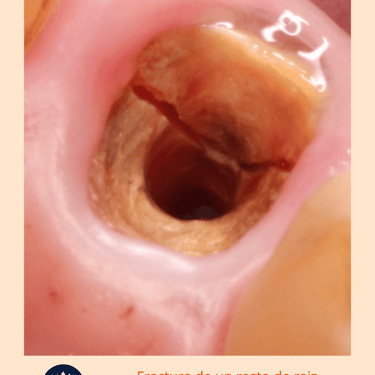

Examen Clínico: El dentista examina el diente y las encías en busca de signos de fractura, como movilidad dental, hinchazón o cambios de color.

Prueba de Percusión: Se golpea suavemente el diente para evaluar la respuesta al tacto. Un dolor agudo puede indicar una fractura radicular.